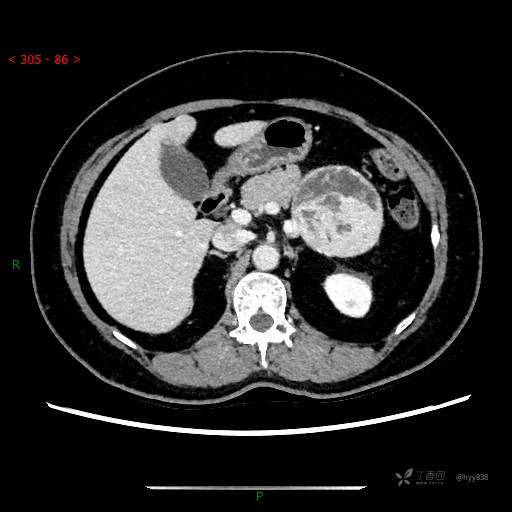

增强动脉期